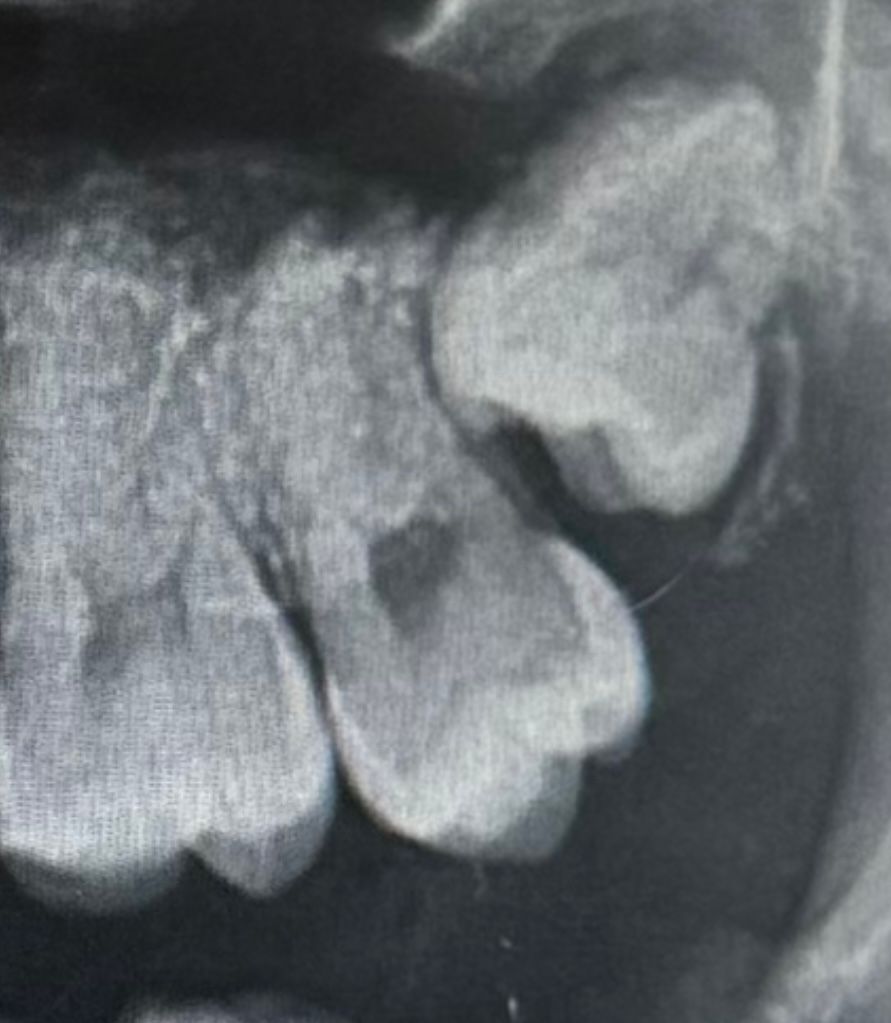

제가 아랫사랑니는 육안으로도 보여서 뽑아야 하구나 생각했는데 윗사랑니는 아직 안보이고 특히나 아프지도 않습니다. 병원에서는 안 뽑아도 될꺼 같다고는 하는데 사진 보시면 알겠지만 이상하게 나서 걱정이 되네요. 다른 병원가서 뽑을까요?

현재 사랑니가 앞의 어금에 닿아있어 방치시에 앞의 어금니를 상하게 하기에 빠른시일내에 발치를 하길 권합니다. 사랑니 발치 경험이 풍부한 구강외과 전문의가 있는 병원에서 발치를 권합니다.

사진상으로는 괜찮고, 별다른 증상이 없다면 현재로선 특별히 무리해서 빼줄 필요가 없는 상악 매복 사랑니로 판단됩니다.